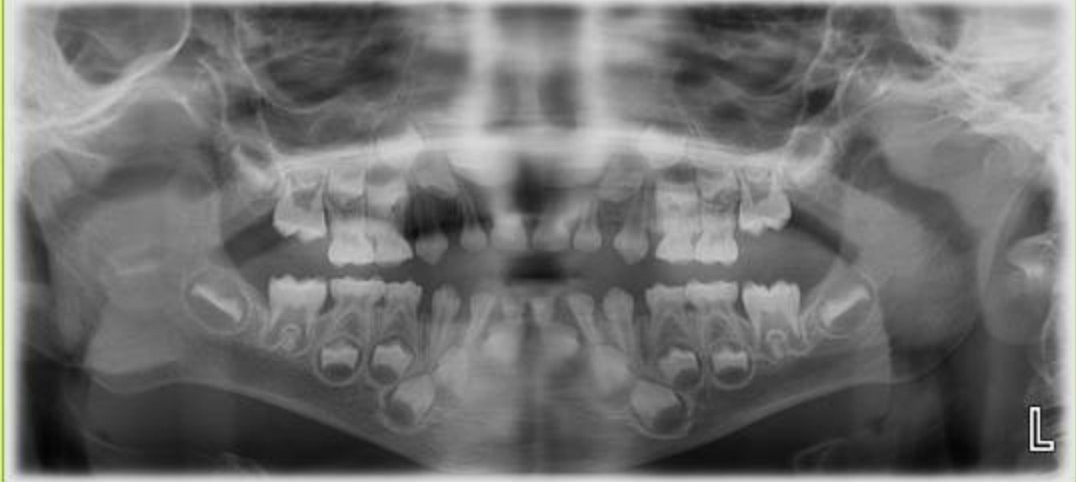

سلام خانم دکتر وقتتون بخیر، پسرمو ماه پیش بردیم دندون پزشکی هر ۶ ماه یکبار وارنیش میزنه دندانپزشک تا دندوناش خراب نشن،بعد اونجا از کل دندوناش یه عکس کلی هم گرفتیم تا مطمئن بشیم ک دندون خراب نداره که داخل عکس دیدیم از زیر لثه دندونای جدید مشخص بودن دقت کردم دیدم دندونای پایینش لق بوده خبر نداشتم،الان تو این سن زود نیست دندونش بیفته یا مشکلی نداره؟پسرم ۴سال و نیم هست

عکسشه

سلام هلیا جان اینکه دندونهای پشتی هم داخل عکس پیداست که طبیعیه

همه ی بچه ها از بدو تولد این دندونهارو دارن

الان طاها ۲۴ تا دندون داره؟

اره عزیزم۲۴تاس،کلا دندون شیریاش زود دراومد برا طاها

اره تو عکس والا هم دندون پشتی ها مشخصن،حالا برام سوال شد چرا دندون پایینی طاها لق شده🥺

افتادن اولین دندان های شیری ممکن است در سن 5 سالگی هم رخ دهد اما اینکه آیا واقعا دندان لق شده و چرا واقعا بدلیل تخصصی بودن با متخصص دندانپزشک اطفال است و من اشراف دقیق ندارم هلیا جانم بهتر است به دندانپزشک نشان دهید

ممنونم دکتر جان بخاطر توضیحات،همسرم میگن پسرمو برده بودن دندانپزشکی اونجا ب دکتر گفتن ک دندون پایینی طاها لق شده مشکلی نداره از الان دندون دربیاره؟ک دکترم گفتن نه مشکلی نداره.دندون پزشک کودک هم بودن،ولی خب ما نمیدونیم الان میخواد دندون دربیاره یا نه فقط لق شده🥲

چون من تو عکس دندونش دندونای داخل لثه رو دیدم گفتم حتمالا داره دندون درمیاره ک فرزانه جان اون بالا عکس دندون پسر گلشو فرستاد گفت اون دندونای داخل لثه طبیعیه حتما برا این نیس ک بخواد دندون جدیدش الان دربیاد